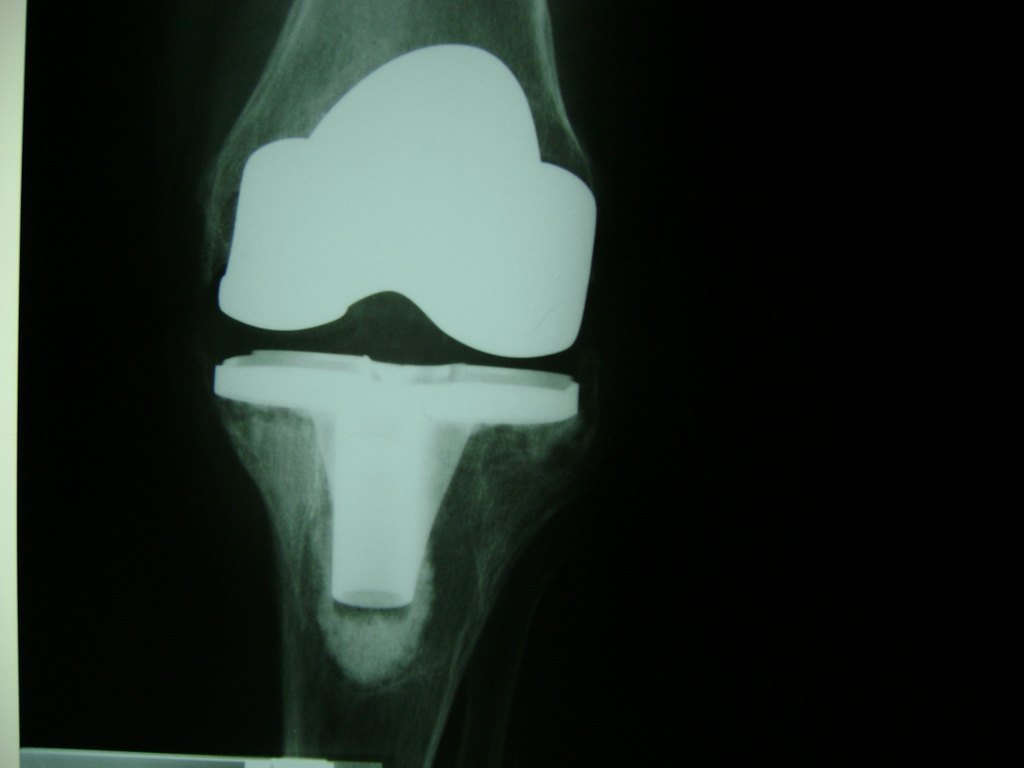

Cirugías de Calcaneo - Rodilla